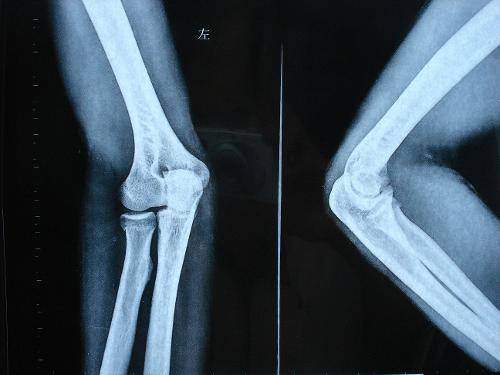

康復(fù)訓(xùn)練的后期已達(dá)到臨床愈合或已經(jīng)去除外固定,此時(shí)骨性骨痂已形成,X線檢查已顯影,骨骼有了一定的支撐力,但大多存在鄰近關(guān)節(jié)的關(guān)節(jié)活動(dòng)度下降、肌肉萎縮等功能障礙。此期康復(fù)的目的是恢復(fù)受累關(guān)節(jié)的關(guān)節(jié)活動(dòng)度、增強(qiáng)肌肉的力量,使肢體功能恢復(fù)??祻?fù)訓(xùn)練主要形式是傷肢關(guān)節(jié)的主動(dòng)活動(dòng)和負(fù)重練習(xí),使各關(guān)節(jié)迅速恢復(fù)到正?;顒?dòng)范圍和肢體的正常力量?;謴?fù)期進(jìn)行康復(fù)的同時(shí)可配合理療及步態(tài)訓(xùn)練等。